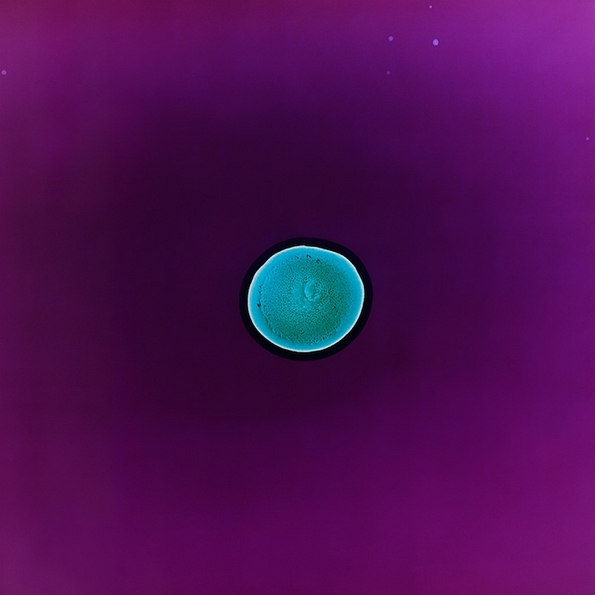

Кокаин

Па така, решила да го спроведе овој проект и успеала да направи одлични фотографии. Таа капнала по неколку капки од различни илегални и легални дроги на филм за апарат кој претходно бил осветлен. Во реакција со филмот, супстанците се зголемиле и рашириле во аморфни форми и живописни бои, што резултирало со одлични фотографии. Таа ја нарекла серијата фотографии „All You Can Feel“.